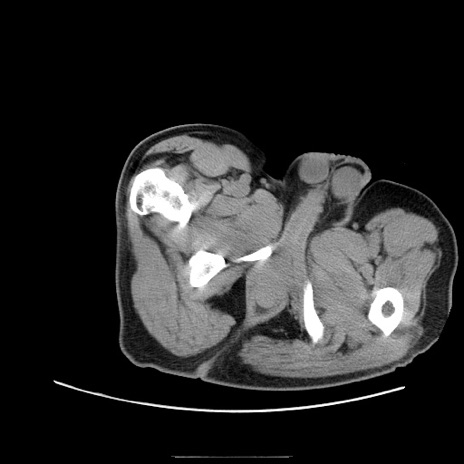

冠状断像

【症例】50歳代男性

【主訴】腹痛

【現病歴】AVMからの被殻出血のため回復期リハ病棟入院中。 本日午後3時頃急に下腹部痛が出現した。

【既往歴】AVM、被殻出血、虫垂炎、高血圧

【身体所見】意識晴明、左半身不全麻痺、会話の理解は良好、36.5°C、腹部:膨隆、全体に板状硬、下腹部正中に圧痛点あり、反跳痛-、筋性防御不明、右下腹部にope scar

【データ】WBC 9400、CRP 0.06